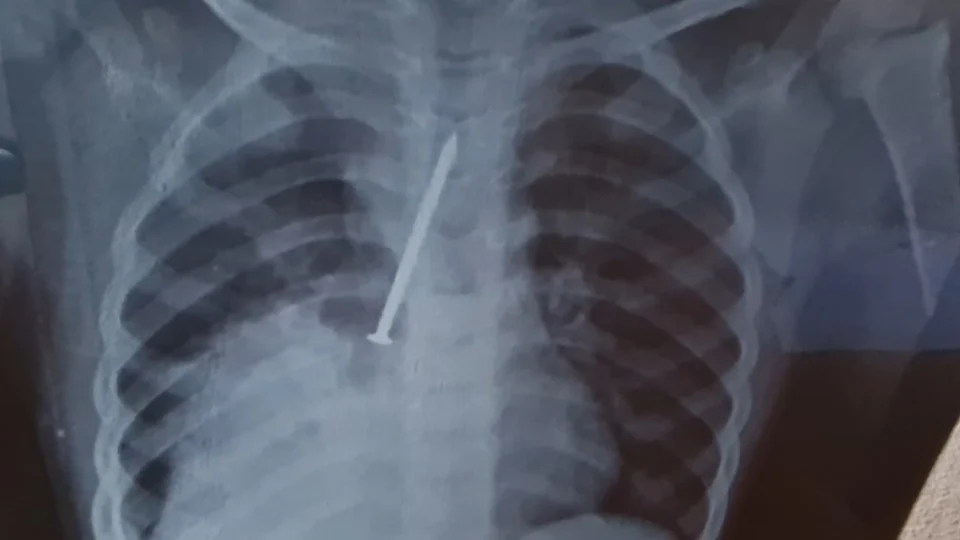

Insatisfeitos, os pais da criança resolveram fazer um exame raio-x particular. Foi quando identificaram a gravidade do problema do filho, que foi transferido para o Hospital Geral do Estado (HGE), onde o garoto passou por uma cirurgia, mas não resistiu.